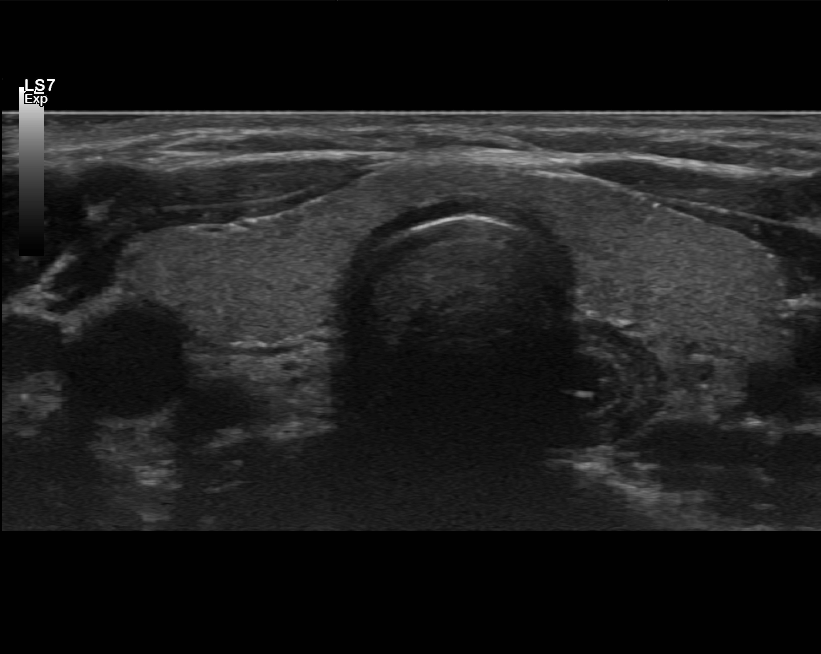

Kaulan ja kilpirauhasen ultraäänitutkimus

- Kilpirauhasen kyhmyt

- Poikkeavat imusolmukkeet